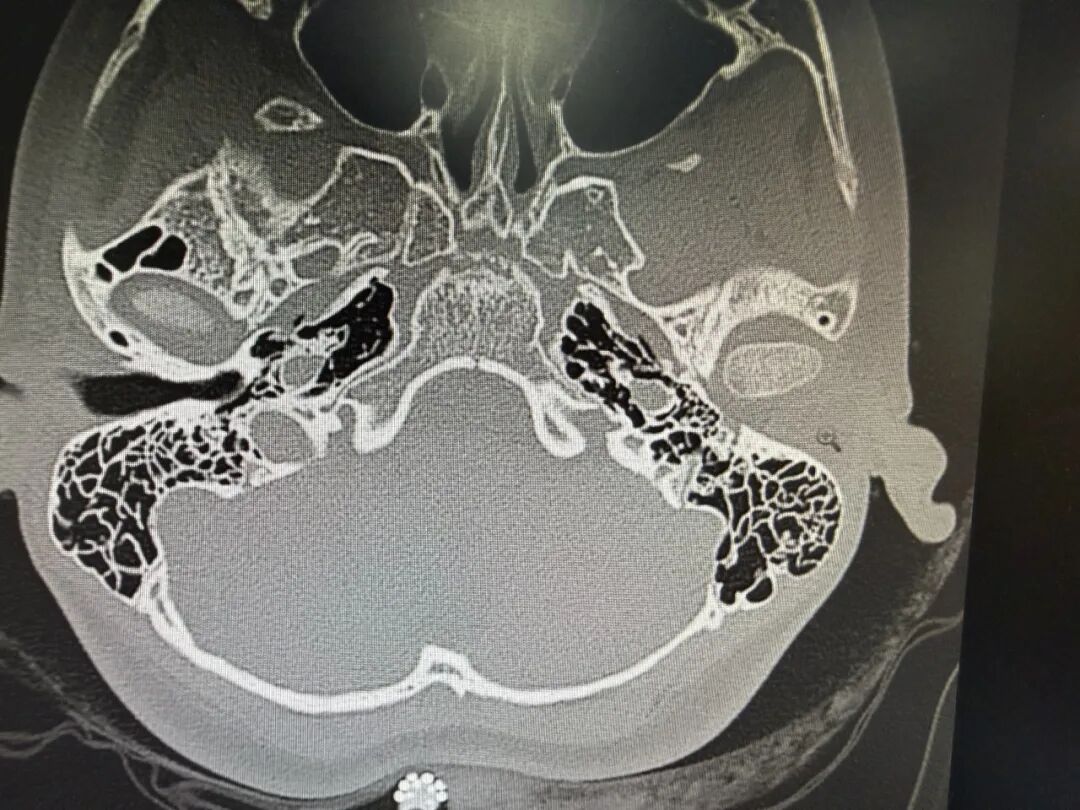

丁医生为女孩做了详细的听力学检查和影像学评估,最终给出诊断:先天性外耳道闭锁(III型),中重度传导性耳聋,听小骨畸形。

“外耳道完全没有,这类手术难度确实很高。”丁医生指着CT片耐心解释,“不过好在孩子的乳突发育尚可,我们可以通过乳突来开辟一个新的外耳道,重建声音传导的通路。”